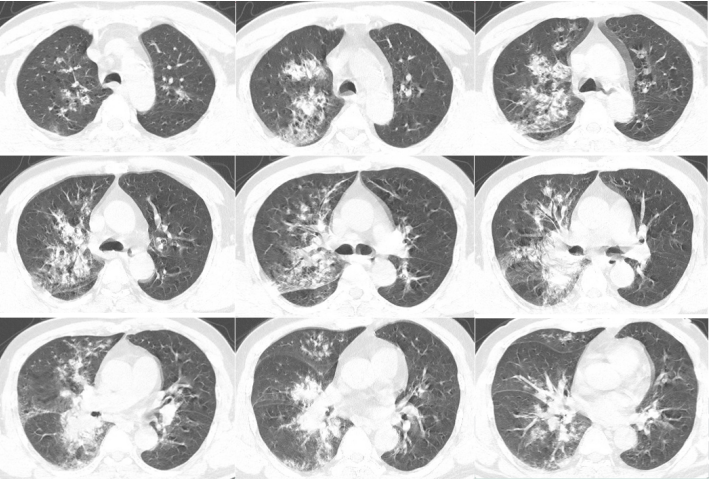

患者60岁女性,因“咳嗽、咳痰20余年,喘息10余年,加重2天”于2016年2月25日入院。

病史:支气管扩张症20余年,受凉后咳嗽、咳痰及喘息症状反复发作;14年前和12年前两次气管插管有创机械通气;长期家庭无创正压通气;入院2天前受凉后出现高热,体温39.6℃,呼吸困难加重。

既往史:高血压10年。

入院时血气分析(吸氧2 L/min):pH 7.32,PaCO2 73 mmHg,PaO2 61 mmHg,HCO3- 30.9 mmol/L,BE 11.5 mmol/L。

入院当天因意识障碍,气管插管后转入RICU。胸部CT见图2。

图片

图2  病例2入院后胸部CT

先后多次调整呼吸机参数及模式(V-A/C模式,Vt由350 ml上调至550 ml;P-A/C模式,压力由24 cmH2O上调至28 cmH2O),PaCO2波动于100~130 mmHg,PaO2波动于60~80 mmHg;拟行肺移植。等待肺移植过程中,患者逐渐出现少尿,尿量最少至475 ml/24h,NT-proBNP最高升至24332 pg/ml,心脏彩超示右心明显增大,肺动脉收缩压估测60 mmHg,予利尿、扩血管、改善心功能等治疗无明显改善,考虑右心功能不全加重。

建立VA-ECMO,患者血氧饱和度仅为75%。胸外科医师考虑于VA-ECMO辅助下行肺移植术的安全性及可行性小,因此一直未实施移植手术。VA-ECMO支持18天,患者心功能改善,周身浮肿消退。将VA-ECMO更换为VAV-ECMO,过渡肺移植。术后1天撤离VV端,转为VA-ECMO辅助。术后4天撤离ECMO。